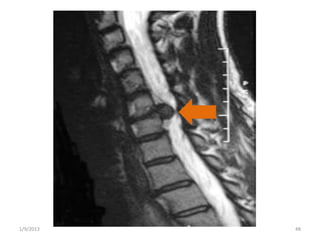

• #48 Cervical axial T1-weighted image (arrow shows disc prolapse

• #49 Sagittal MRI showing disc prolapse compressing the spinal theca and distorting the cervical cord.

• #50 Sagittal MRI showing disc prolapse compressing the spinal theca and distorting the cervical cord.